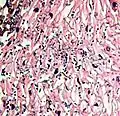

- A severe case of candidiasis

In most cases, the diagnosis is established based on response to therapy. Patients in whom esophageal candidiasis is suspected should receive a brief course of antifungal therapy with fluconazole. If the infection resolves after treatment with fluconazole, then the diagnosis of esophageal candidiasis is made and no further investigation is needed. However, if the infection persists or if there are other factors involved which may warrant further investigation, then patient will undergo an esophagogastroduodenoscopy if it is safe to do so. Endoscopy often reveals classic diffuse raised plaques that characteristically can be removed from the mucosa by the endoscope. Brushing or biopsy of the plaques shows yeast and pseudohyphae by histology that are characteristic of Candida species.